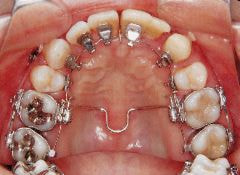

治療例1 (インプラント補綴+矯正)